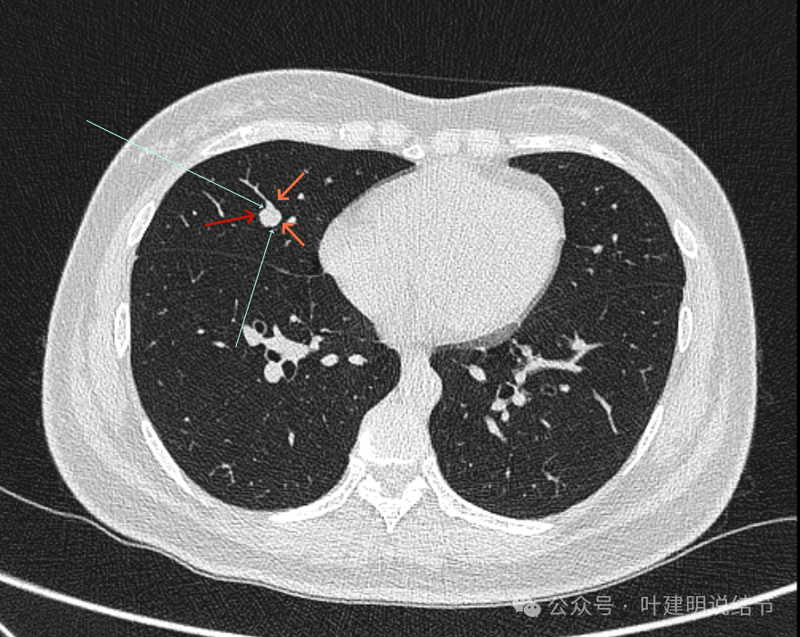

再看冠状位影像:

血管与病灶的关系,两者密度稍不同,天蓝色细箭头所指是分界线。

血管征明显。

血管围着病灶,病灶有膨胀性,表面欠平滑。

不而有膨胀性,血管贴着并被压迫。

边缘欠平滑,邻近血管间隙欠清晰。

血管贴着,结节膨胀。

也示血管与病灶的关系。

结节实性。

纵隔窗这个角度明显见到蓝色箭头所指的血管被病灶侵蚀,而且血管与病灶密度的不同。